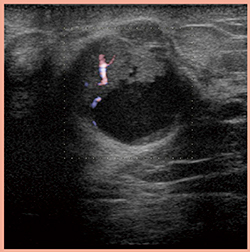

また,より低流速での血流形態評価も4G CMUT+eFocusingで可能となった(図6)。

図6 4G CMUT+eFocusingによる

より低流速な血流形態評価